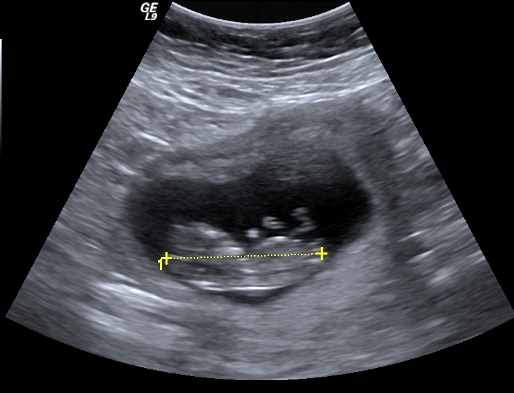

I finally managed to get hold of my u/s disc and have selected a few of the pics I think could have a nub in them (I'm still pretty hopeless at working out nubs).

There is only 1 pic from my 19 week scan that even comes remotely close to the bottom region and I'm pretty sure it is not a potty shot, just of legs from above I think??? (second last pic...biggest one)...I'm a little p'd off with the tech as I asked him to get a pic for me and he obviously didn't.

Just driving myself crazy here and I am coming up 29 weeks...not likely to get another scan any time soon if at all so hoping for any guesses at all!!!